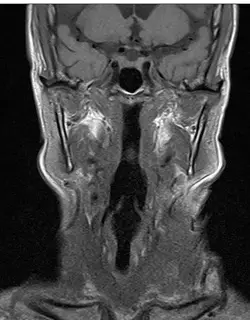

頭頸部腫瘤患者的影像如下圖,此可能是何種權重之 MRI 影像?

- 解剖切面:這是一張頭頸部的冠狀切面 (Coronal view) MRI 影像。

- 脂肪訊號 (Fat Signal):觀察影像中臉部兩側的皮下脂肪 (Subcutaneous fat)、副咽間隙 (Parapharyngeal space) 等富含脂肪的區域,皆呈現高訊號 (亮白)。這可以直接判斷該影像沒有使用脂肪抑制技術。

- 水/液體訊號 (Fluid/Water Signal):觀察影像上方腦部周圍的蜘蛛膜下腔及腦池 (即腦脊髓液 CSF 所在之處),呈現低訊號 (黑色/暗色)。

- 肌肉與空氣:兩側的咀嚼肌 (如嚼肌、翼肌) 呈現中等訊號 (灰色);咽喉呼吸道內的空氣則呈現極低的無訊號 (黑色)。

- 骨髓:下顎骨支 (Mandibular ramus) 內的骨髓因富含脂肪,同樣呈現高訊號。

- (A) T1WI:在 T1 權重影像中,主要特徵為「脂肪亮、水暗」。本圖皮下脂肪